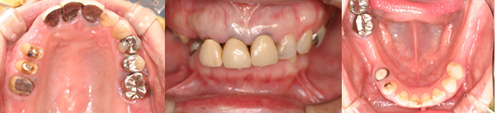

43歳 女性

主訴 奥歯で物が咬めない

治療内容 歯周病治療 咬合治療 インプラント治療 歯内治療(根の治療)

治療前